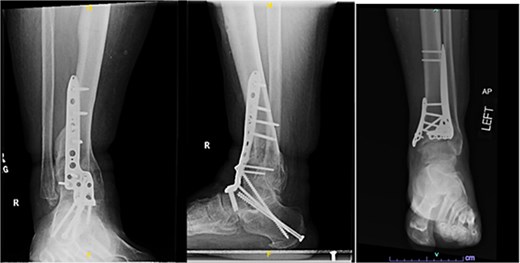

Despite the patient’s noncompliance, he went on to heal uneventfully for the next 2 years until the patient fell from a height of 15 feet, resulting in a left bicondylar tibial plateau fracture and fracture of the left tibial shaft. These injuries required ORIF of his left tibia. Despite the new injury, the hardware from the pilon fractures was in proper alignment (Fig. 4).

Two-year follow-up AP and lateral radiographs of both ankles in patient 2 showing maintained alignment and hardware position.